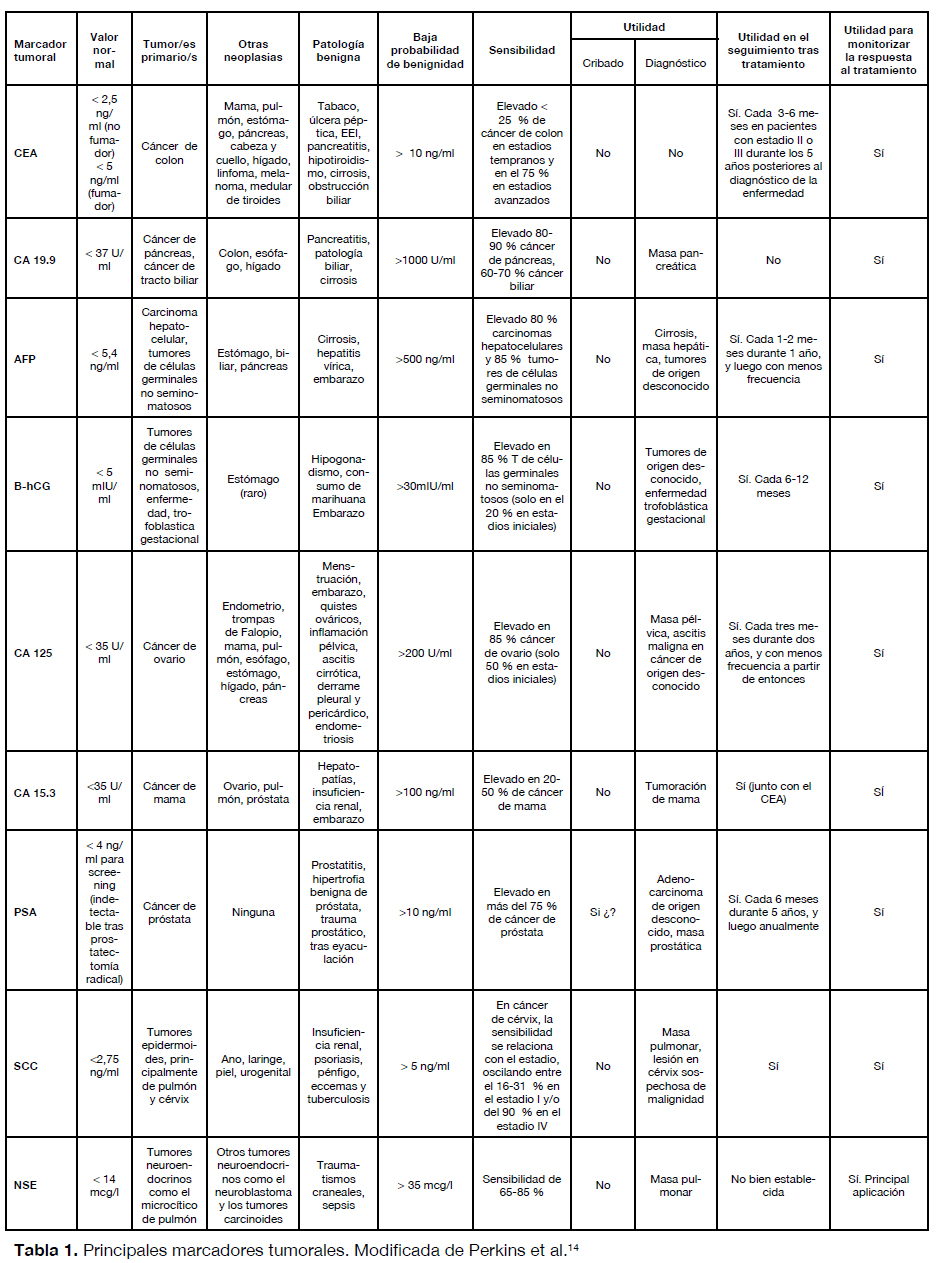

Psicologicamente Shinkan danza Marcadores Tumorales - Marcadores de tumores NCI Puntos clave Los marcadores de tumores son - Studocu

Pase para saber Psicológico pueblo Marcadores tumorales en el diagnóstico de cáncer epitelial de ovario: caso de estudio Tumor markers in the diagnosis of epit